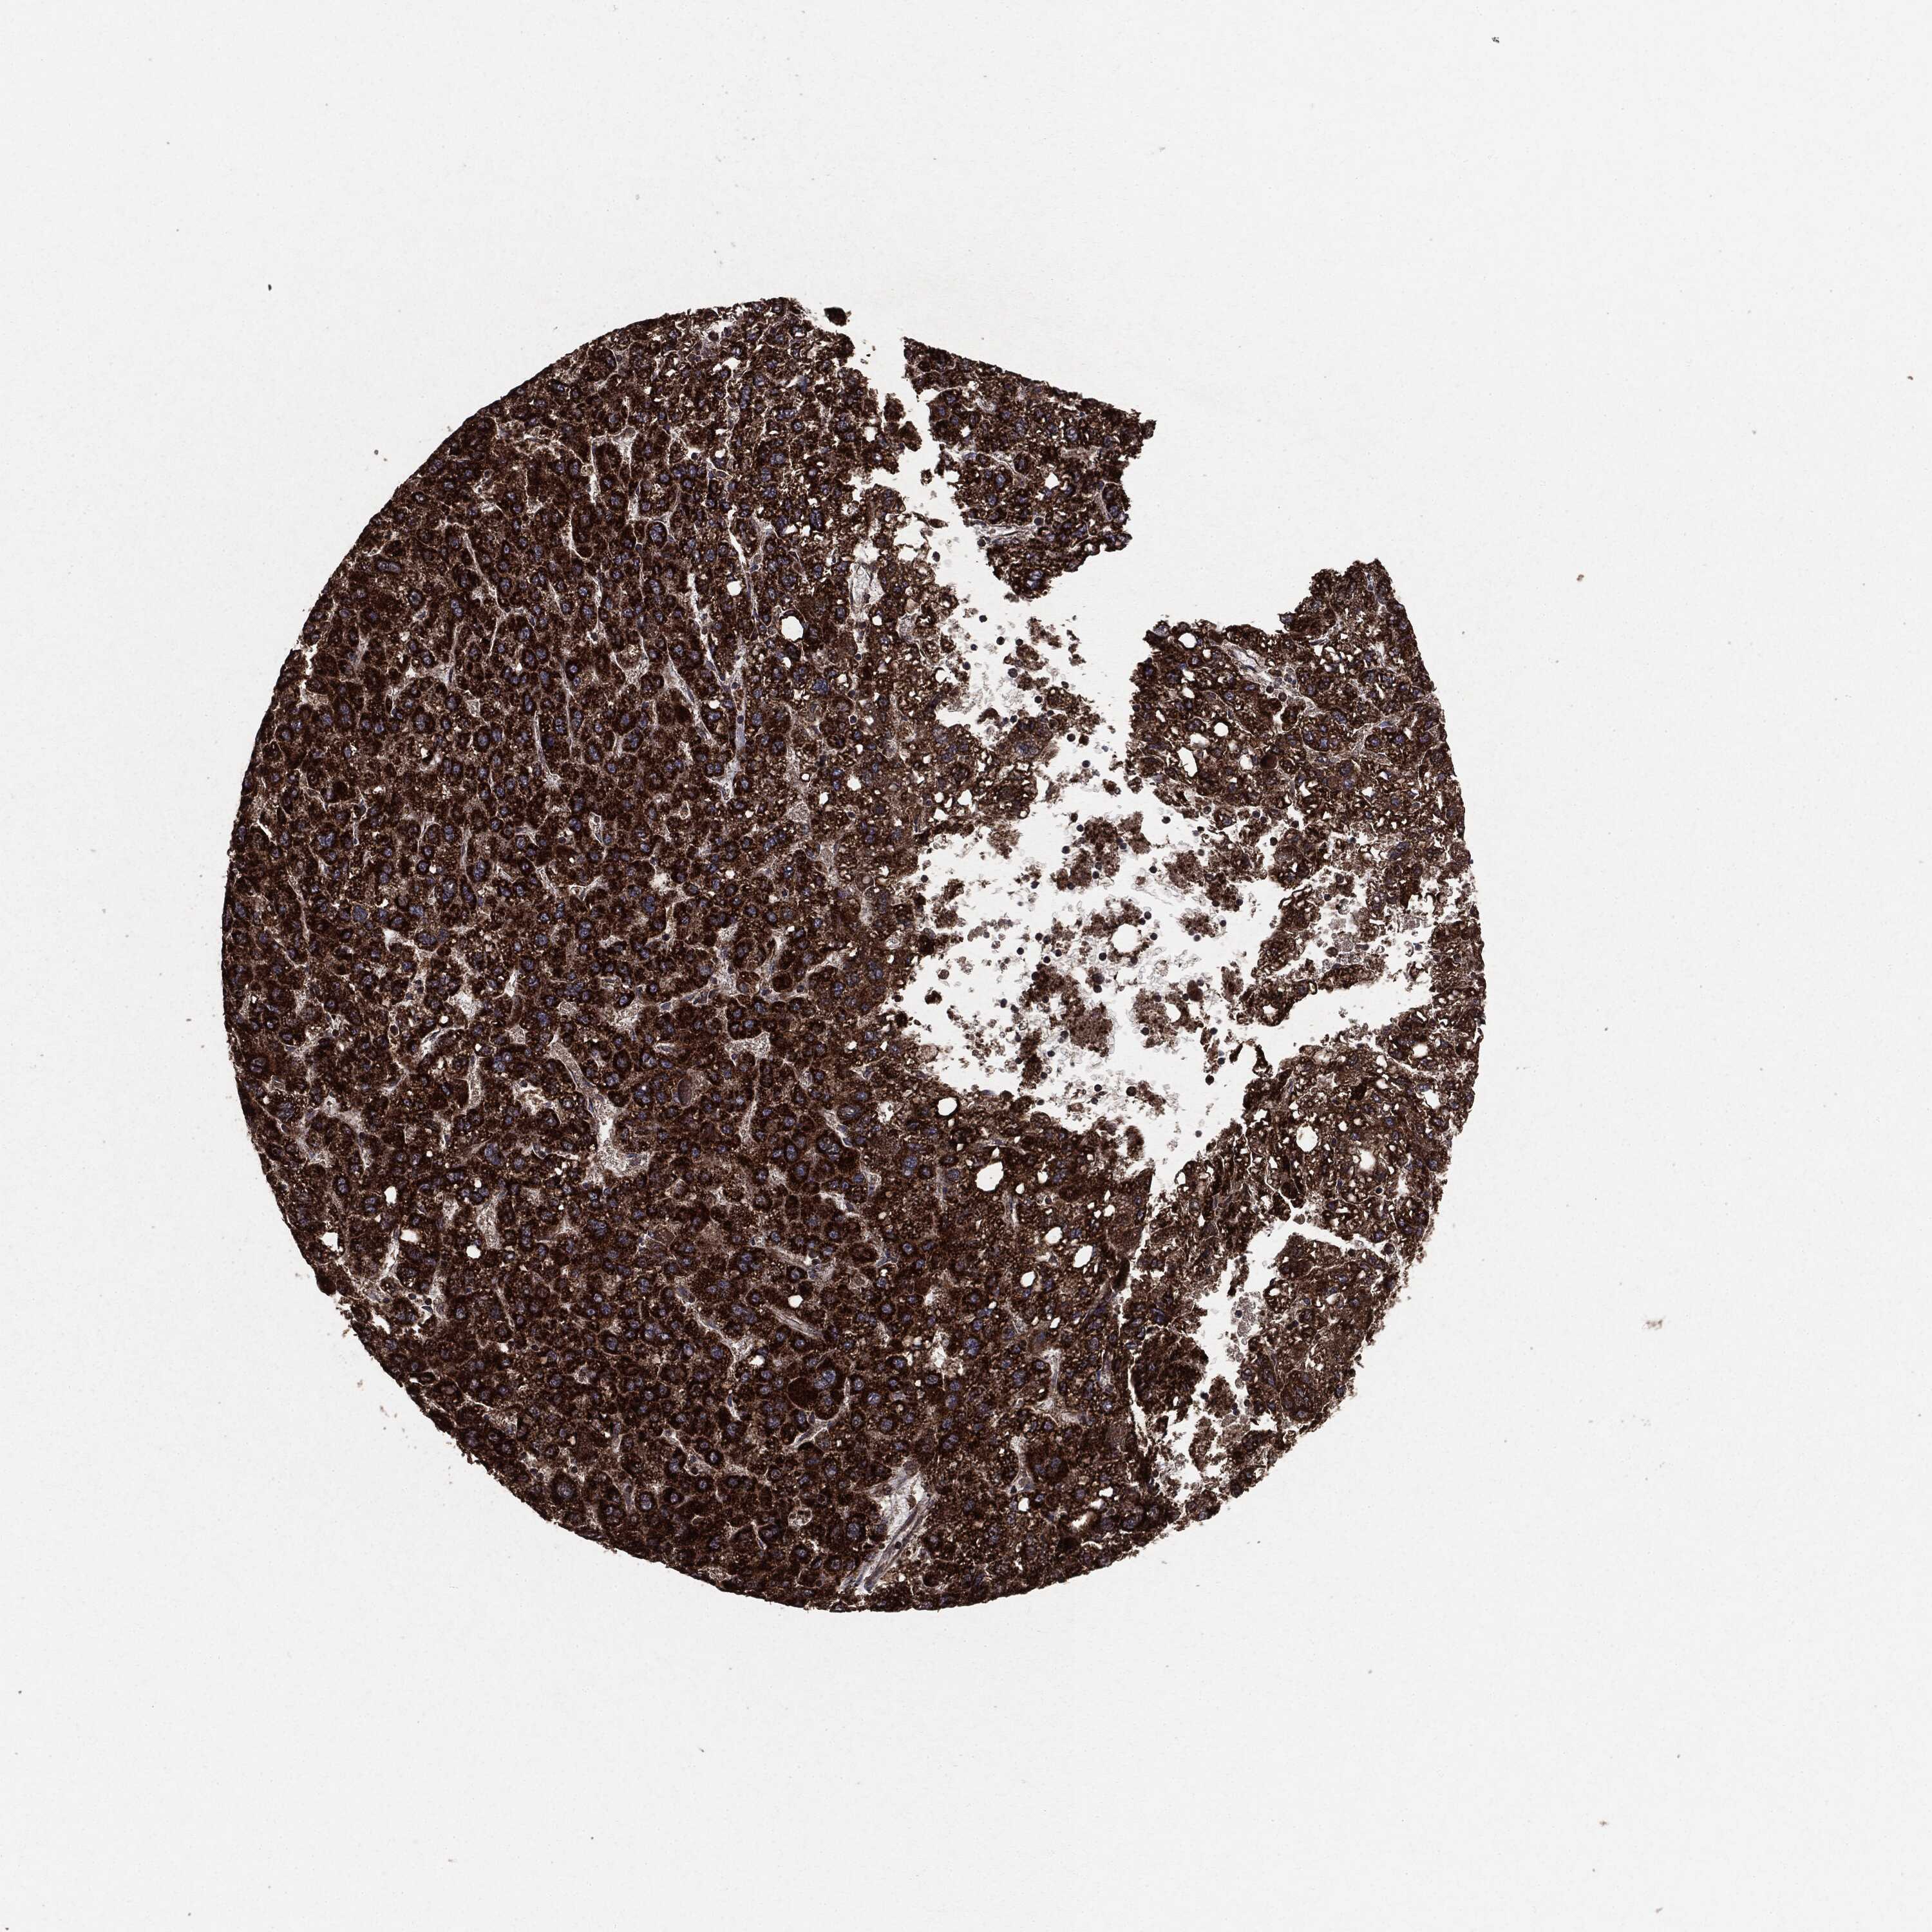

LIVER CANCER - Protein expressioni

A mouse-over function shows sample information and annotation data. Click on an image to view it in a full screen mode. Samples can be filtered based on level of antibody staining by selecting one or several of the following categories: high, medium, low and not detected. The assay and annotation is described here.

Note that samples used for immunohistochemistry by the Human Protein Atlas do not correspond to samples in the TCGA dataset.

Antibody stainingi

Antibody staining in the annotated cell types in the current human tissue is reported as not detected, low, medium, or high, based on conventional immunohistochemistry profiling in selected tissues. This score is based on the combination of the staining intensity and fraction of stained cells.

Each image is clickable and will lead to virtual microscopy that enables deeper exploration of all samples and also displays staining intensity scores, fraction scores and subcellular localization as well as patient and tissue information for each sample.

Carcinoma, Hepatocellular, NOS